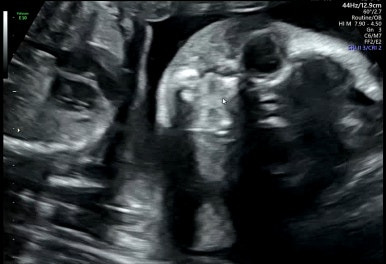

25주 1일

일반 정기 검진으로 태아의 성장을 점검하고 특이사항이 없으면 다음 검진 때 간다.